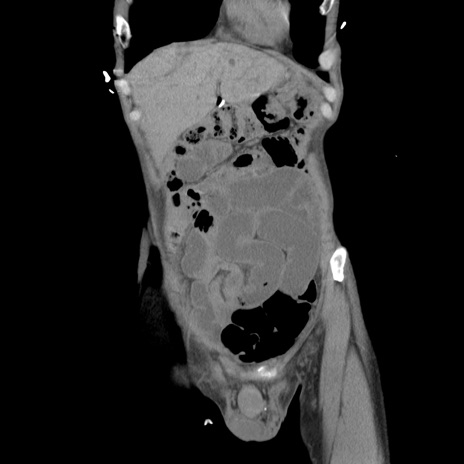

症例11(冠状断像)

【症例】 60歳代男性

【主訴】 下腹部痛

【現病歴】 本日夜中より下腹部痛の症状認め、受診。

【既往歴】 膀胱癌(膀胱全摘+尿管皮膚瘻術) 、胃癌術後

【身体所見】 BT 35.3℃、PR 58/min、BP 136/98mHg、腹部平坦、軟、腸蠕動音±、ストマ留置あり、左上腹部~正中部に圧痛あり、反跳痛なし。

【データ】WBC 5100、CRP0.01